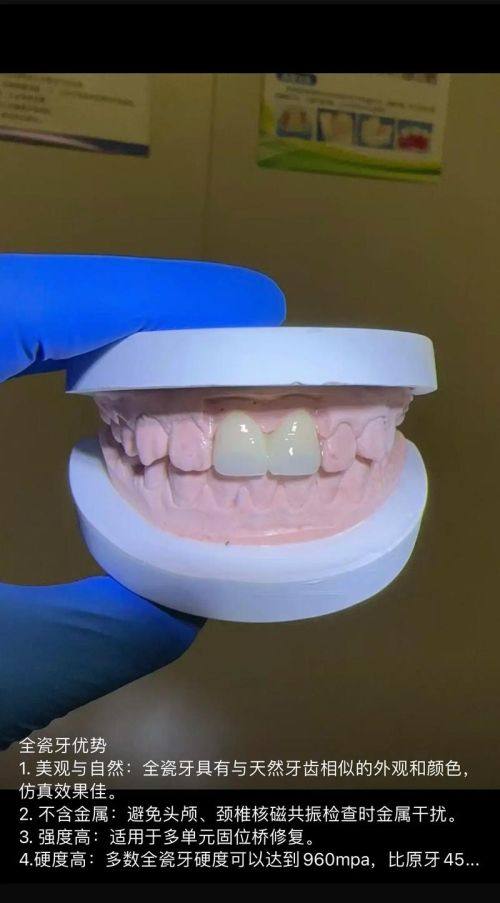

6. 全瓷牙:2000 - 5000元